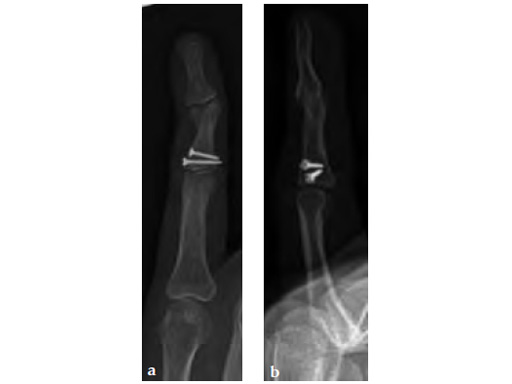

A 22-year-old female with previous complex fractures of the base and head of the middle phalynx (proximal screws are from the previous fracture fixation) presented with a residual painful, deformed, and stiff DIP J. Joint arthrodesis planned.

Case provided by Robert Farnell, Leeds, UK

The arthrodesis was performed using the longest available screw. Note that despite this it has only just crossed the arthrodesis site (see Fg 2a-b)